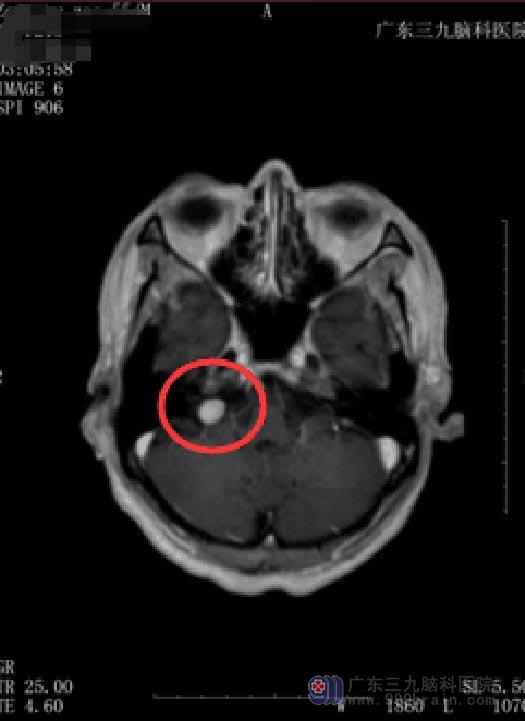

肿瘤临近脑干,术后可能出现的并发症多,手术风险比较大。经家属同意后,在全麻下行“右侧桥小脑角占位切除术”,术中脑干,后组颅神经,椎动脉等重要组织保护良好,手术非常成功。术后没有出现后组颅神经损伤的情况,曾大叔恢复得很快,已经出院。术后病理结果:神经鞘瘤。

![(曾汝早术后)7VUDJ(]COQ$V9AH@}D$TPIK.jpg](/upload/news/NewsContent/2018/2018-09/20189291558764.jpg)